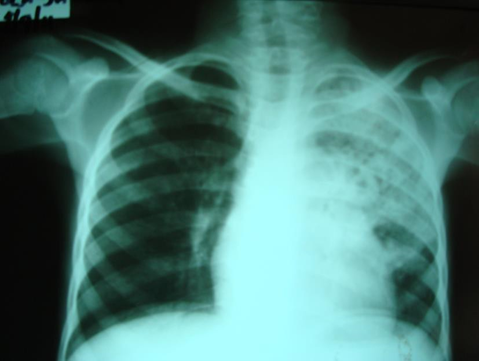

Presentation: The signs and symptoms of CMV disease often overlap with other infectious processes, therefore, the diagnosis of CMV disease in HIV-infected children should take into consideration clinical presentation and radiological finding along with laboratory testing. CMV pneumonia presents with fever, dyspnoea and hypoxemia. A chest radiograph shows diffuse pulmonary infiltrates (ground glass appearance) as seen in other viral pneumonias and PCP. The isolation of CMV from isolates including BAL does not prove that the child has CMV pneumonia. Co-infection with both PCP and CMV is common.